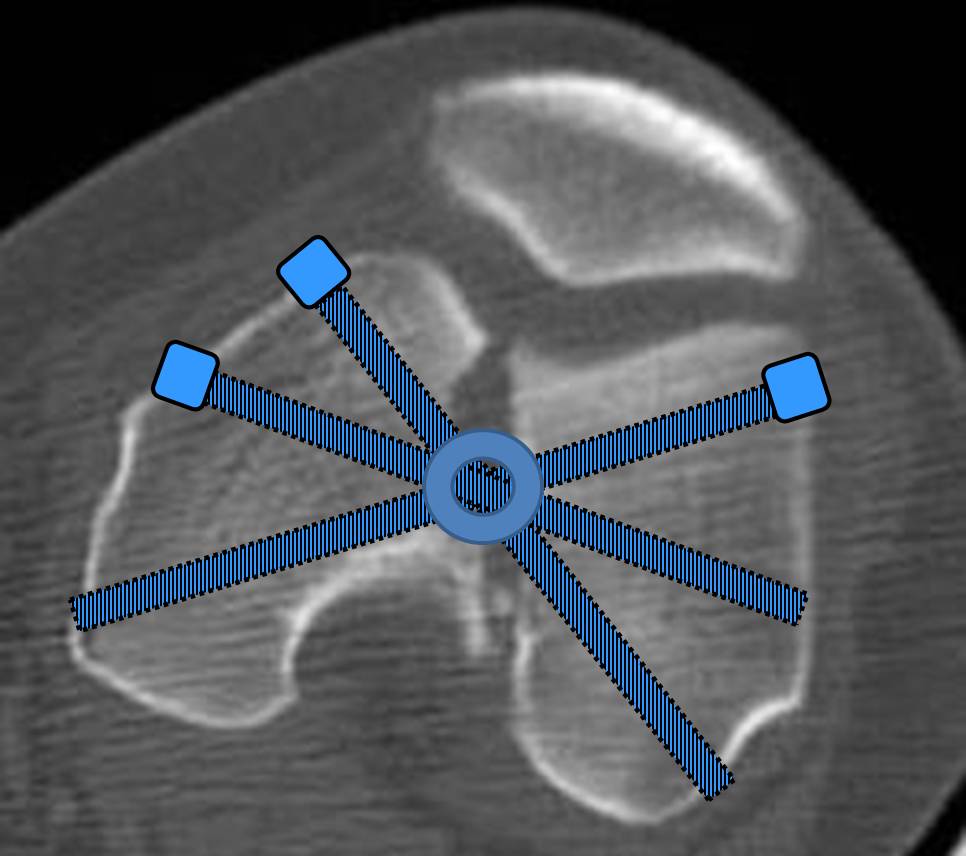

И уже лет шесть мы используем возможность ввести в дистальное овальное отверстие 3 винта, которые именно запираются в этом отверстии, не люфтят, а обеспечивают угловую стабильность - см картинку.

Получается и стабильно, и очень дистально, нижний край отверстия в 3 мм от дистального конца гвоздя.

Рационально ориентироваться на качественный аспект - проблема или решается, или нет. Переломы типа 33C1 или C2 (то есть без фронтального раскалывания мыщелков, как на показанной Вами томограмме) при обычном качестве кости успешно можно фиксировать гвоздями с фронтальными винтами. Получается, их прочностных характеристик уже достаточно.

В приложении пример недавней операции, C3, открытая репозиция, фиксация мыщелков спицами и винтами, ретроградный синтез большеберцовым гвоздем 10,5 мм диаметром, винты 5 мм.

Наш гвоздик, выпускаемый предприятием ЦИТО, тоже скорее из универсальных, хотя и с расширенными возможностями для дистальных переломов. Это овальное отверстие внизу задумывалось как динамическое для высоких переломов, очень дистально его разместили, чтобы не опасаться перелома гвоздя по этому отверстию. А возможность вот такого введения винтов, образующих "сборный клинок", обнаружилась года через 3 его применения.

Но практика показывает, что классификации существуют не зря, и стоит пользоваться ими, а не ориентироваться на абстрактные "максимально низкие переломы". Подавляющее большинство поступающих к нам больных с дистальными переломами - это C1 и С2. И показанный в прошлом сообщении гвоздик прекрасно справляется. Наверно, сгодятся и многие современные гвозди разных производителей, типа RAFN Synthes. А вот при настоящих C3 одним гвоздем не обойтись, нужны как минимум винты мимо, а то и введение на одном уровне нескольких винтов и/или спиц веером...